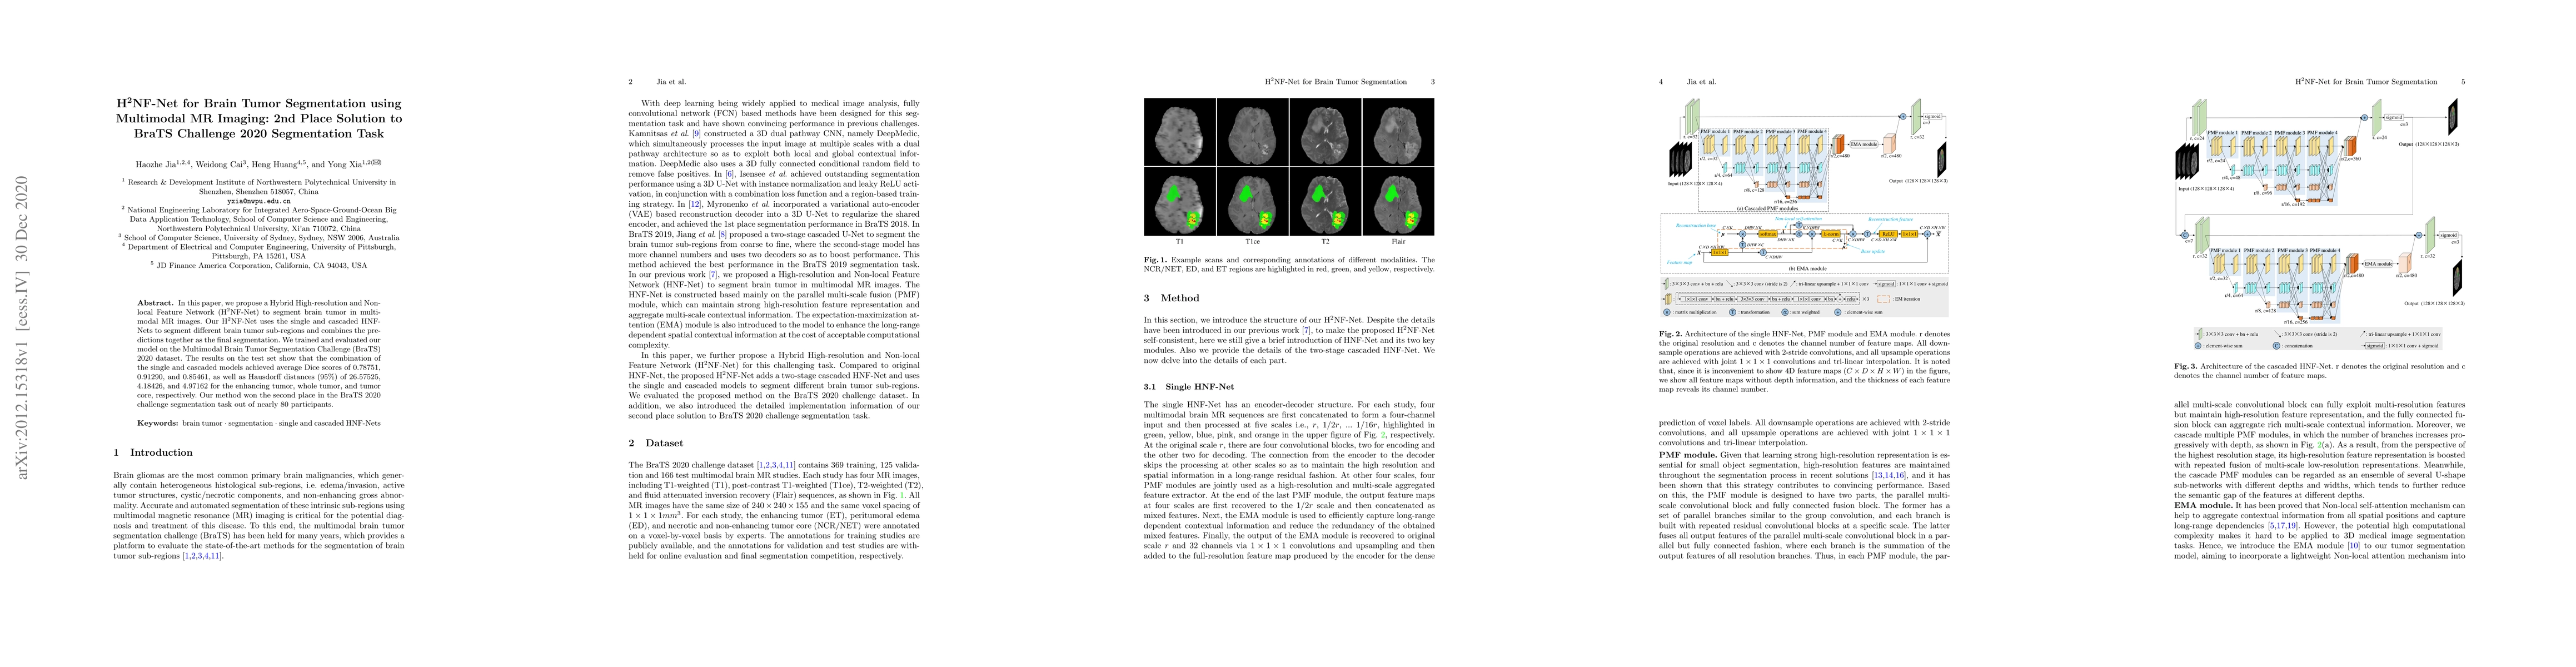

In this paper, we propose a Hybrid High-resolution and Non-local Feature Network (H2NF-Net) to segment brain tumor in multimodal MR images. Our H2NF-Net uses the single and cascaded HNF-Nets to segment different brain tumor sub-regions and combines the predictions together as the final segmentation. We trained and evaluated our model on the Multimodal Brain Tumor Segmentation Challenge (BraTS) 2020 dataset. The results on the test set show that the combination of the single and cascaded models achieved average Dice scores of 0.78751, 0.91290, and 0.85461, as well as Hausdorff distances ($95\%$) of 26.57525, 4.18426, and 4.97162 for the enhancing tumor, whole tumor, and tumor core, respectively. Our method won the second place in the BraTS 2020 challenge segmentation task out of nearly 80 participants.